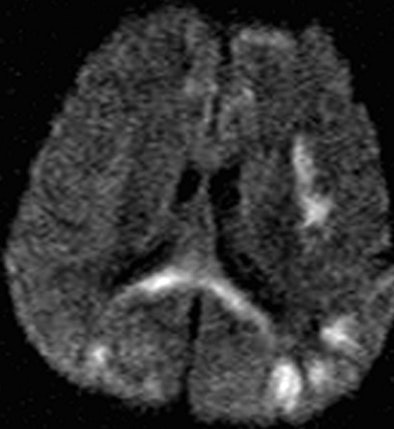

Above is a T2-weighted MR image of bilateral patchy hyperintense lesions in the cerebral cortex, including the insula (arrow). There is also involvement of the splenium of the corpus callosum (arrowhead). On the corresponding diffusion-weighted MR image below, the hyperintense lesions are more prominent than above. |